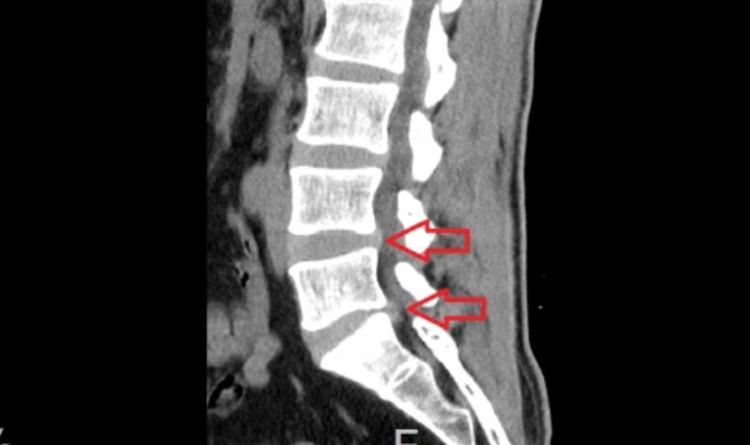

하지만 이 상태에서 질환이 더욱 악화되면 후방 섬유륜이 더욱 찢어지게 되고 그 크기가 커지면 디스크 안에 있던 수핵이 밖으로 튀어나오게 됩니다. 이것을 허리디스크가 터졌다고 표현을 하며 의학용어로는 요추 추간판 탈출증이라고 합니다.

디스크 밖으로 튀어나온 수핵이 척추에 연결된 신경을 누르거나 염증반응을 일으켜 요통과 함께 다리가 아프고 저린 좌골신경통 증상이 동반되게 됩니다.